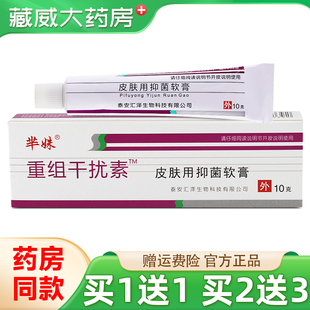

原价 13.9销量 0

¥13.9

华虎医药专营店